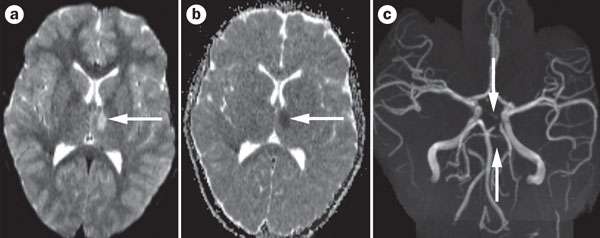

يمكن لتصوير الأوعية بالرنين المغناطيسي ( MRA ) أن يقيم الأوعية الدماغية و يظهر منطقة نقص التروية الدماغية.